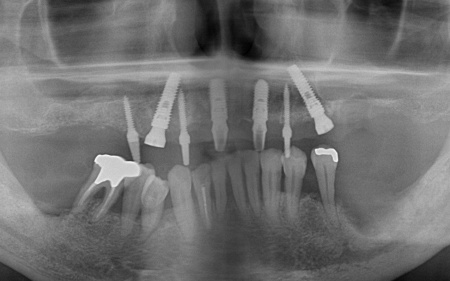

50代男性 抜歯と同時にインプラントを埋めて歯を補った症例

「転倒して上前歯のブリッジがとれた。他院で上あごの総入れ歯をすすめられたが、ほかに方法がないか知りたい」とセカンドオピニオンとしてご来院いただきました。

拝見したところ、患者様は上前歯が数本欠損しており、残っている歯を利用して橋渡しのように歯を補うブリッジ治療が行われていました。しかし、転倒による衝撃でブリッジが外れていました。

また、患者様は重度の歯周病によって歯を支える骨が減少し全体的に歯が揺れていました。

残っている上の歯7本(左右上側切歯、左右上犬歯、左右上第1小臼歯、左上第1大臼歯)と右下奥歯2本(第2大臼歯、第3大臼歯)は残すことが難しく抜歯が必要な状態です。

以上のことから、抜歯を行ったうえで歯を補う治療が必要と診断しました。

インプラント治療が可能かどうかを調べるためレントゲンとCTの撮影を実施したところ、インプラントを支えるのに十分な骨の量があり問題なく治療できることが確認できました。

①上の歯7本、右下の奥歯2本を抜歯する。上あごには抜歯と同時に4本のインプラントを埋め、その上に10本分の仮歯を取り付けるオールオンフォーを行う。

インプラントの種類には、あごの骨と結合する力に優れたオステム社のETⅢを採用。インプラントが骨にしっかり定着するまでの間は、通常のインプラントよりも細い暫間インプラントを一時的に併用して仮歯を支える